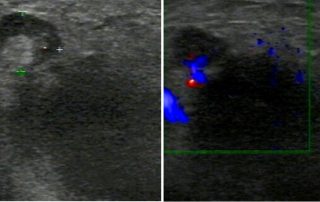

Läsion und deren Diagnose

Eine 75-jährige Patientin, V G, IV P, die drei Mal verwitwet wurde und sehr sporadisch und selten zur Untersuchung kam, stellte sich zur Routine-Untersuchung vor. Bei ihr war ein Uterusmyom bekannt, sonst hatte sie gynäkologisch eine blande Vorgeschichte. Bei der Untersuchung erzählte sie, dass sie vor der vierten Heirat stehe.